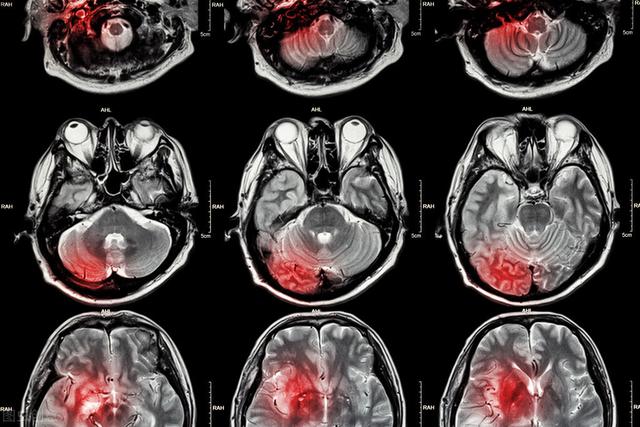

Les médecins peuvent recommander divers tests de diagnostic, tels que les suivantsCT crânien ou IRM crânienne, échographie carotidienneCes tests permettent de déterminer la cause de la maladie.

● Certaines personnes peuvent avoir besoin d'examens complémentaires, tels queAngiographie par tomodensitométrie, angiographie cérébrale ou surveillance ECG ambulatoire de 24 heuresLe médecin de l'hôpital doit être informé de l'évolution de l'état de santé du patient, afin de rechercher d'éventuelles causes vasculaires ou cardiaques.

En général, le médecin confirme le diagnostic et propose un plan de traitement basé sur un test de préhension des mains du patient, une prise de tension artérielle, un scanner de la tête et une IRM si nécessaire. Les médicaments vasodilatateurs et les médicaments qui nourrissent les vaisseaux sanguins sont généralement préférés, et l'aspirine tend à devenir un médicament courant pour certains patients à partir de ce moment-là.

Étant donné que la durée des symptômes chez les patients souffrant d'un accident ischémique transitoire n'est pas longue, la plupart des patients semblent normaux lorsqu'ils consultent le médecin, mais ils devraient également améliorer les examens tels que la tomodensitométrie crânienne ou l'imagerie par résonance magnétique. Si l'examen d'imagerie ne révèle aucune lésion d'infarctus cérébral, le diagnostic d'accident ischémique transitoire devrait être posé et, en même temps, une hémorragie cérébrale peut être exclue, car elle peut également présenter des symptômes similaires. À ce stade, bien que les symptômes aient été soulagés, cela ne signifie pas qu'aucun autre diagnostic et traitement n'est nécessaire, et il est encore nécessaire d'améliorer l'angiographie par tomodensitométrie, l'angiographie par résonance magnétique ou l'angiographie, etc., pour clarifier la gravité des lésions vasculaires dans la tête et le cou, afin de guider l'élaboration d'un plan de traitement raisonnable.Il est important de noter queAu stade précoce de l'infarctus cérébral, les foyers d'infarctus cérébral ne peuvent être détectés par le scanner ou l'IRM, et la durée maximale d'un accident ischémique transitoire est de 24 heures ; comment différencier un accident ischémique transitoire d'un infarctus cérébral au cours de cette période de 24 heures ? La résonance magnétique pondérée en diffusion permet de détecter les premiers foyers d'infarctus cérébral.

Après l'apparition d'un accident ischémique transitoire, la réduction du risque d'infarctus cérébral par un traitement approprié est de la plus haute importance. Les accidents ischémiques transitoires peuvent être causés par des lésions athérosclérotiques, par des thromboembolies cardiaques ou par des anomalies hémodynamiques telles que l'hypotension ou l'hypovolémie. Les options thérapeutiques varient en fonction de la cause : pour les lésions athérosclérotiques, il s'agit de retarder l'athérosclérose, de stabiliser la plaque artérielle et d'utiliser des médicaments antiagrégants plaquettaires pour prévenir la thrombose ; pour les embolies d'origine cardiaque, il s'agit d'utiliser des anticoagulants ; et pour les patients présentant des anomalies hémodynamiques, il convient d'administrer un supplément de volume sanguin afin de corriger l'hypoperfusion. Si l'examen révèle une sténose sévère des artères de la tête et du cou, telle qu'une sténose de 70 % ou plus, la nécessité d'un traitement chirurgical tel qu'une endartériectomie carotidienne ou la pose d'un stent doit également être évaluée. Un traitement rationnel des causes à haut risque d'infarctus cérébral, telles que l'hypertension, le diabète sucré et la dyslipidémie, doit également être mis en place afin de réduire le risque d'infarctus cérébral.

Bien entendu, si l'infarctus cérébral s'est déjà produit, un traitement raisonnable doit être administré dès que possible au stade précoce de l'infarctus cérébral, ce qui contribuera à améliorer le pronostic. Le stade précoce de l'infarctus cérébral se situe entre trois et six heures après l'apparition de l'infarctus cérébral. À ce moment-là, les cellules cérébrales situées dans la zone des artères cérébrales malades sont encore sauvables et il est possible de sauver les cellules cérébrales mourantes grâce à la thrombolyse intraveineuse ou à la thérapie interventionnelle, qui peut débloquer les artères cérébrales dans le plus court laps de temps possible. Les patients traités dans les trois heures suivant l'apparition de l'infarctus cérébral ont plus de chances de se rétablir complètement ; ceux qui sont traités dans les quatre heures et demie suivant l'apparition de l'infarctus cérébral continuent à voir leur fonction neurologique s'améliorer ; ceux qui sont traités dans les six heures suivant l'apparition de l'infarctus cérébral voient leurs résultats favorables augmenter ; et ceux qui sont traités plus de six heures après l'apparition de l'infarctus cérébral ont déjà perdu leur traitement optimal. Par conséquent, après la survenue d'un infarctus cérébral, la première et principale tâche consiste à arriver à l'hôpital dans les plus brefs délais et à débloquer les artères cérébrales obstruées dès que possible, afin de réduire le taux d'invalidité et le taux de mortalité liés à l'infarctus cérébral.

Il convient de prêter attention à la reconnaissance de l'aura de l'infarctus cérébral : en cas d'accident ischémique transitoire, c'est-à-dire d'apparition d'une faiblesse unilatérale des membres, d'une anomalie sensorielle, de troubles du champ visuel, d'un engourdissement du visage, d'un coin de la bouche tordu, d'une paralysie de la langue, ainsi que de vertiges, de troubles de l'équilibre, de diplopie, etc., mais d'une durée de quelques minutes, généralement d'une heure, ne dépassant pas 24 heures, et si les examens d'imagerie pertinents n'ont pas révélé de foyers d'infarctus cérébral, il s'agit d'une aura de l'infarctus cérébral et le risque d'évolution vers l'infarctus cérébral est élevé. Si aucune lésion d'infarctus cérébral n'est trouvée à l'examen d'imagerie, il s'agit d'une aura d'infarctus cérébral et le risque d'évolution vers un infarctus cérébral est élevé ; il convient donc d'améliorer les examens pertinents et d'administrer un traitement raisonnable pour réduire le risque d'infarctus cérébral. Après la survenue d'un infarctus cérébral, une thérapie thrombolytique ou interventionnelle doit être administrée dès que possible et dans les trois à six heures afin de débloquer les vaisseaux sanguins cérébraux et de réduire les lésions du tissu cérébral.